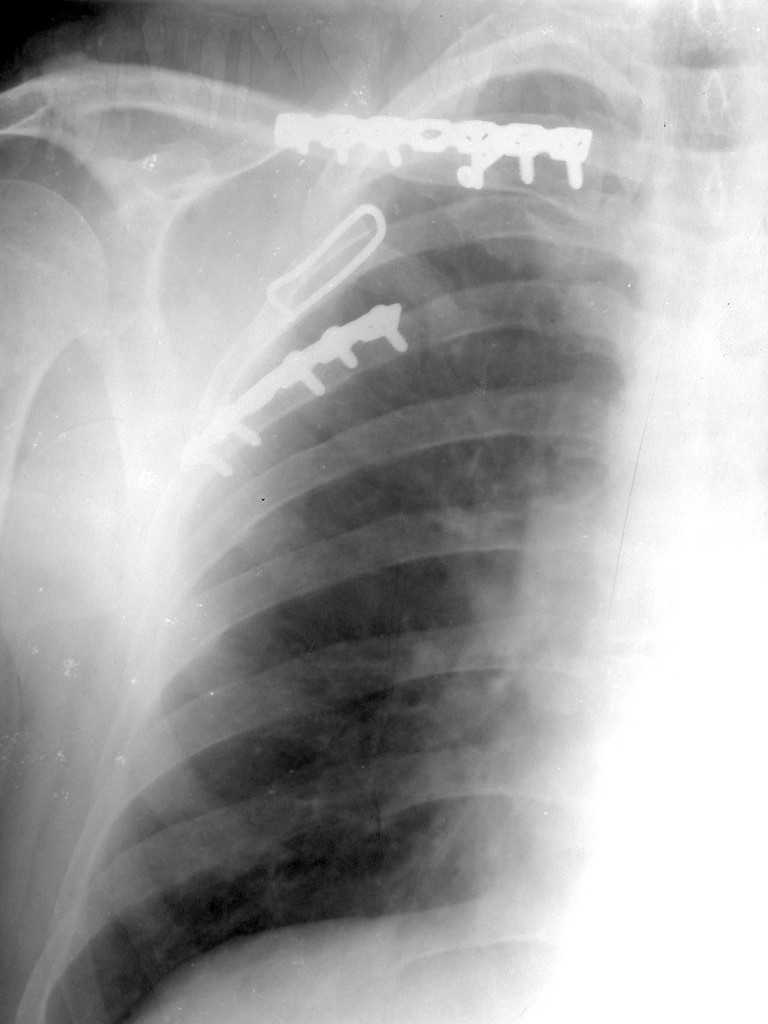

Уважаемые коллеги, помогите определиться с тактикой. Больной 1953гр, травма на стройке, придавило тяжелымпредметом. Сейчас в сознании, стабилен, плевральная полость задренирована. Предполагаем синтез ключицы, если бы не переломы ребер, установили бы шину ЦИТО.Есть у кого опыт открытого/закрытого синтеза подобной лопатки? Что делать с клювовидным отростком? Спасибо, Моисеев Ю.И.

Мы в таких случаях оперируем в 2-а этапа:

1. Стабилизация грудной клетки(фиксируем ребра по одной из линий рекон. LCP)

2. Остеосинтез лопатки из заднего доступа(рекон.LCP, LC-LCP 3,5мм, Т-обр.LCP 3,5мм); ключицу стандартно

К сожелению доктор который занимается грудной клеткой в отпуске, у себя нашёл только вот этот снимок

С Уважением А.Миронов